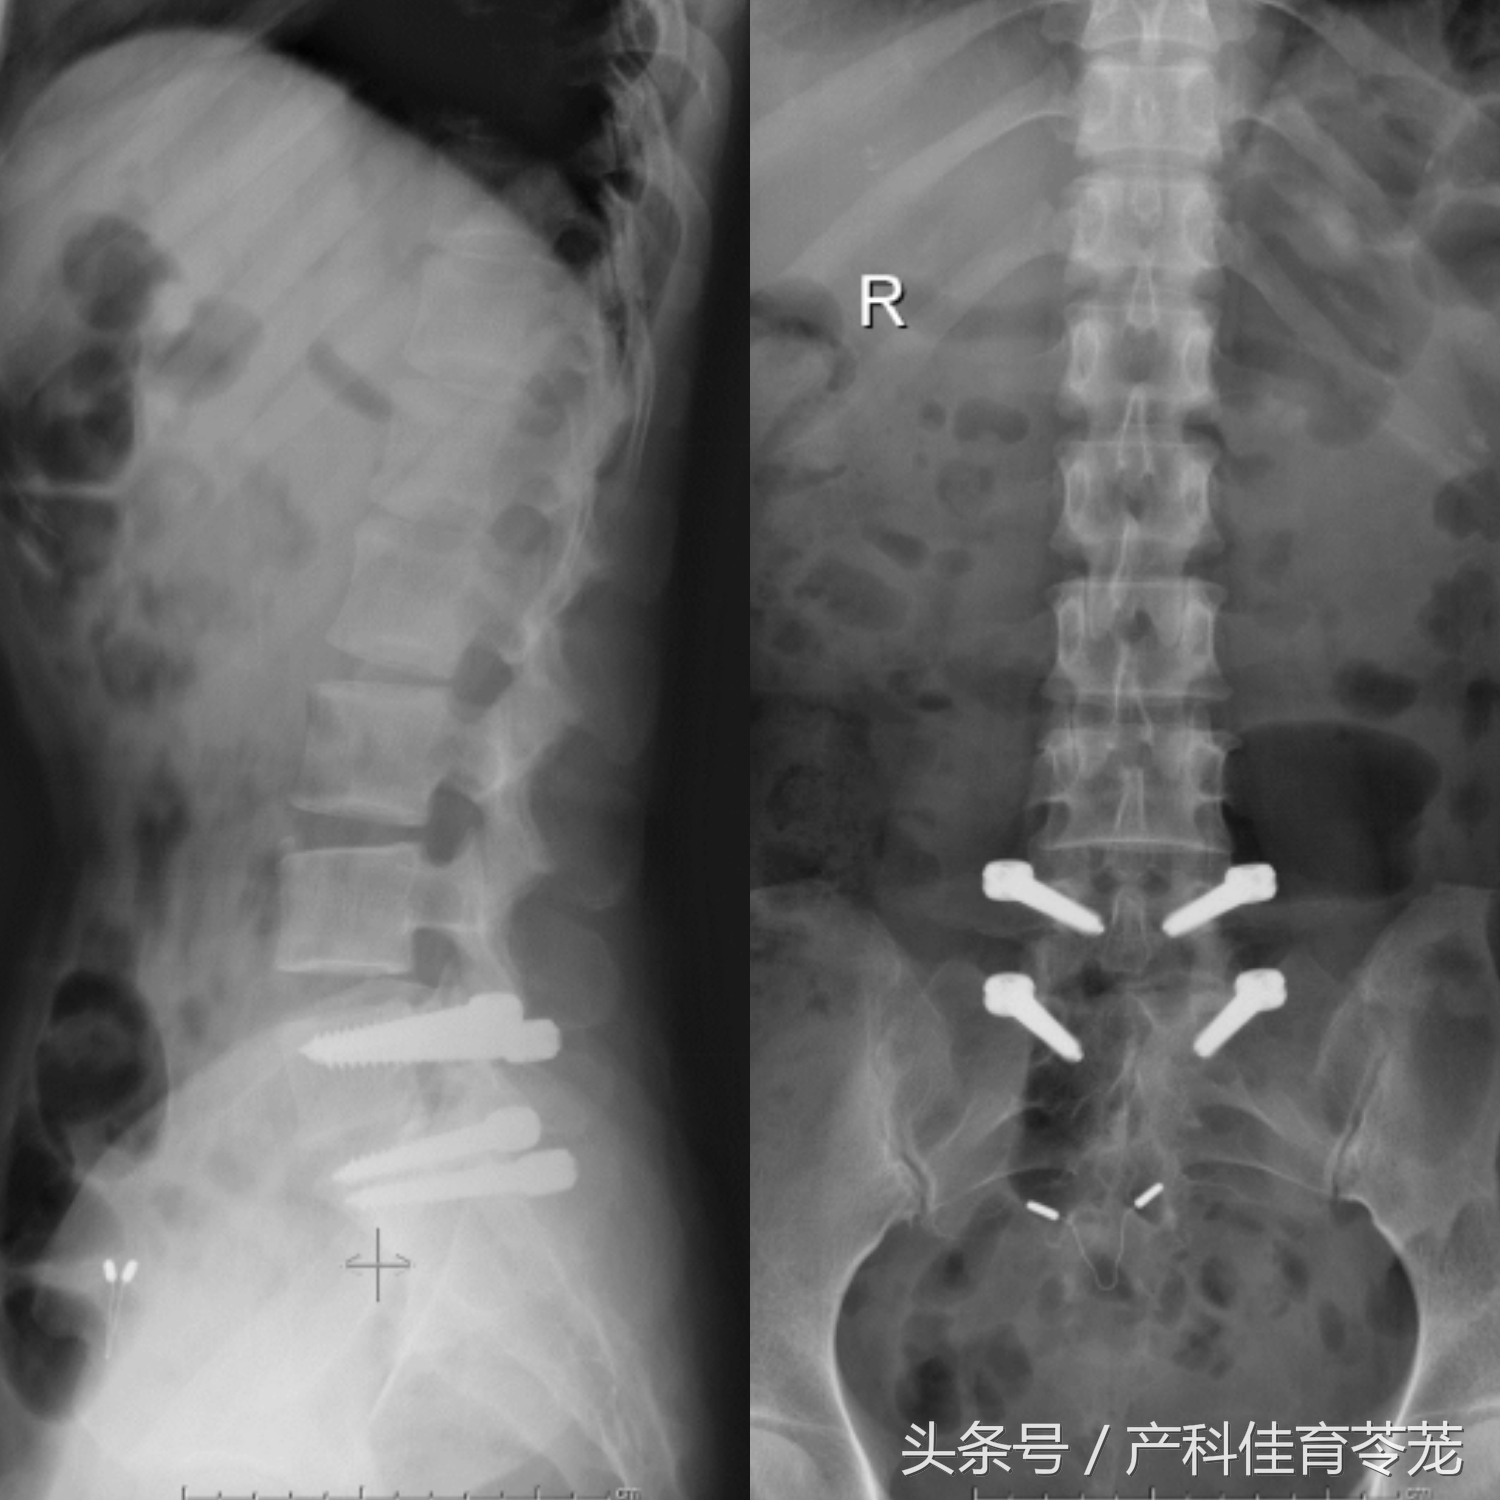

病人做了腰5骶1开窗减压,髓核摘除,并采用腰椎DYNESYS动态稳定系统固定。

术后腰椎片示内固定位置良好: